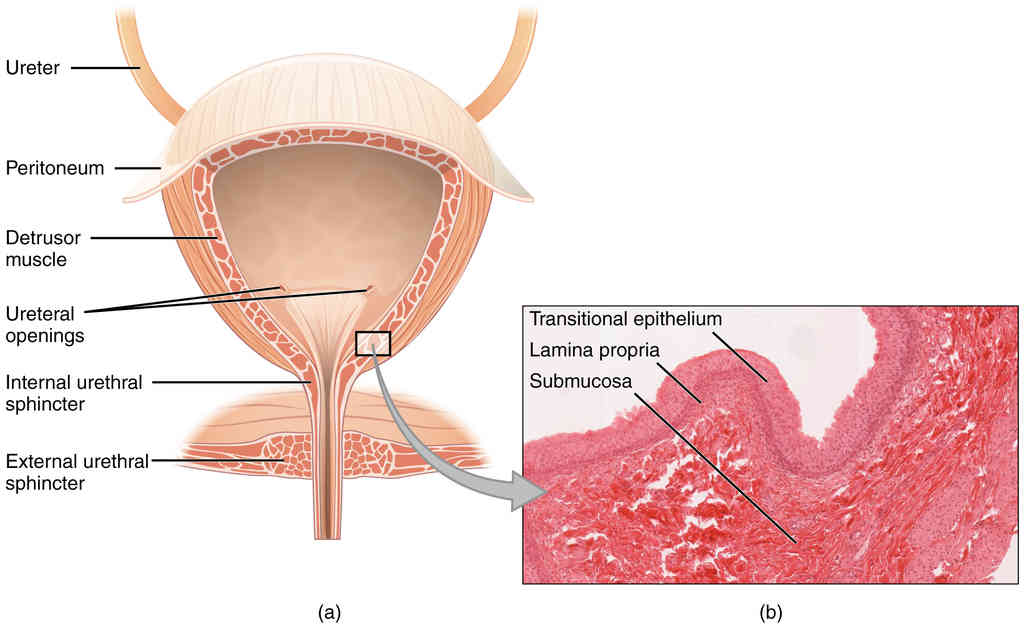

This page is under construction. For now, it is just a resource of the images found in the OpenStax Anatomy and Physiology Handbook. It wil slowly change into a revision tool. Each slide has a number. Use this to refer to the slide. When completed, it will have an unlabelled section, with labelled slides in parallel. On the unlabelled slides, write your answer and use the labelled slide to assess yourself. Keep track by also noting the number on each slide. Improvement at each attempt is important, more so than full marks on a first attempt.